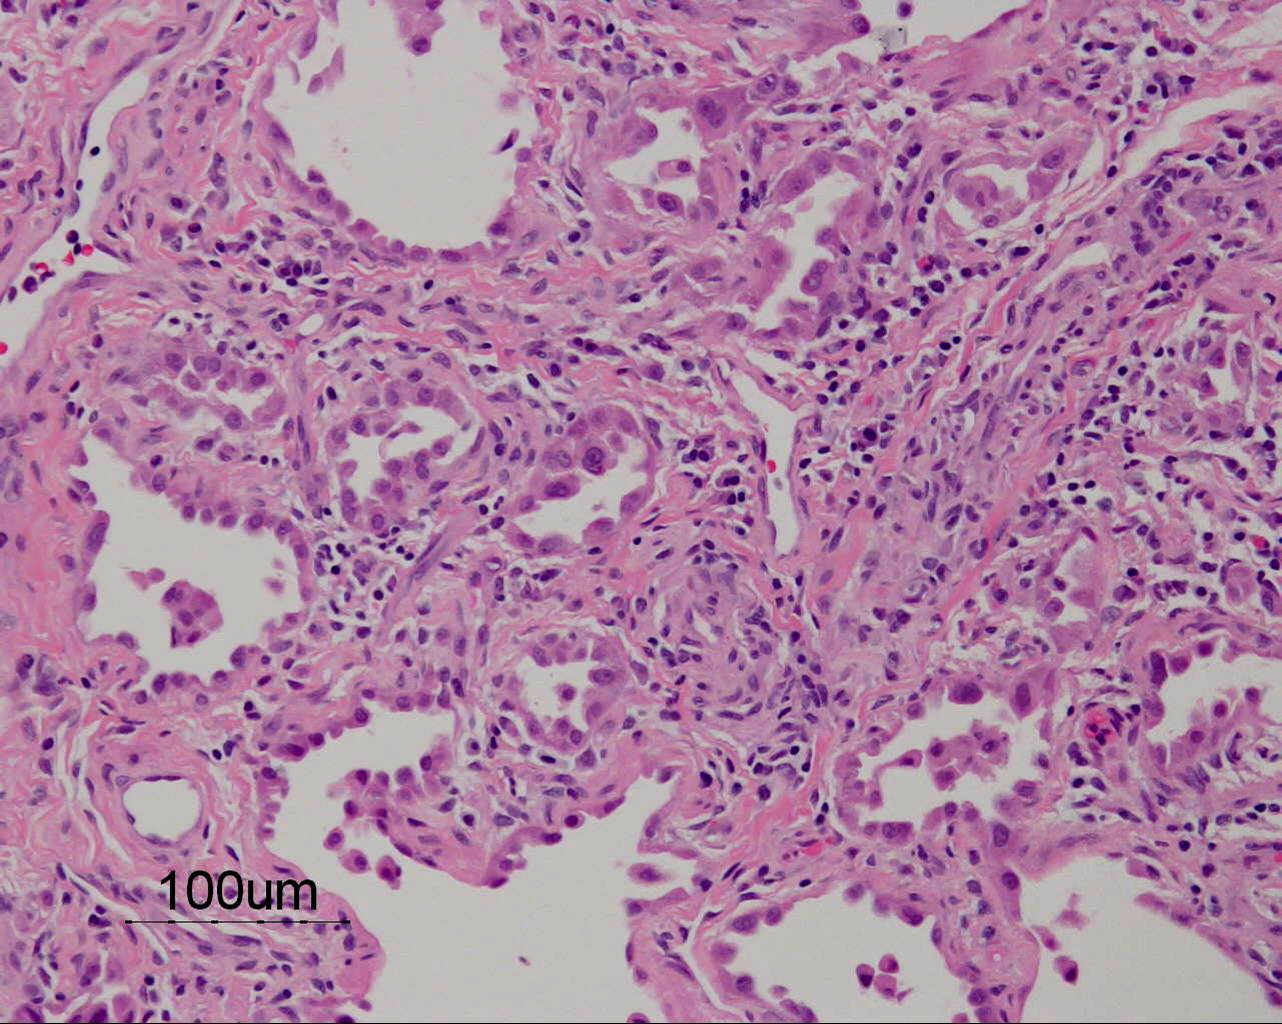

Based on the information found on the CT of the chest, LF underwent an open lung biopsy which showed usual interstitial pneumonitis (UIP) as demonstrated in the pathology below: